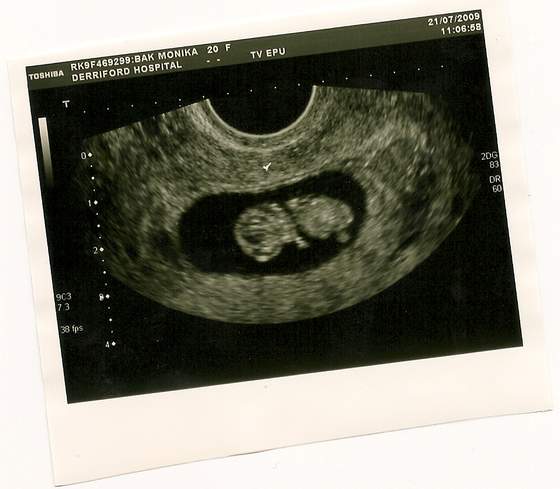

hejka sorki ze sie wczoraj nieodezwalam ale bylismy w domu dopiero po 18 po zakupach i bylam tak wykaczona ze niemilam sil na nic tak wiec moja kochana fasoleczka ma sie bardzo dobrze rosnie jak na drozdzach wszystko jest w jak najlepszym stanie nastepna wizyta 18.08 bedzie juz 12 tyg czyli bedzie malutka dzidzia moja fasolka jest o tydzien starsza nizwychodzi z miesiaczki:-)wklejam zdiatko jak sie uda;-):-)pozdrawiam:-)